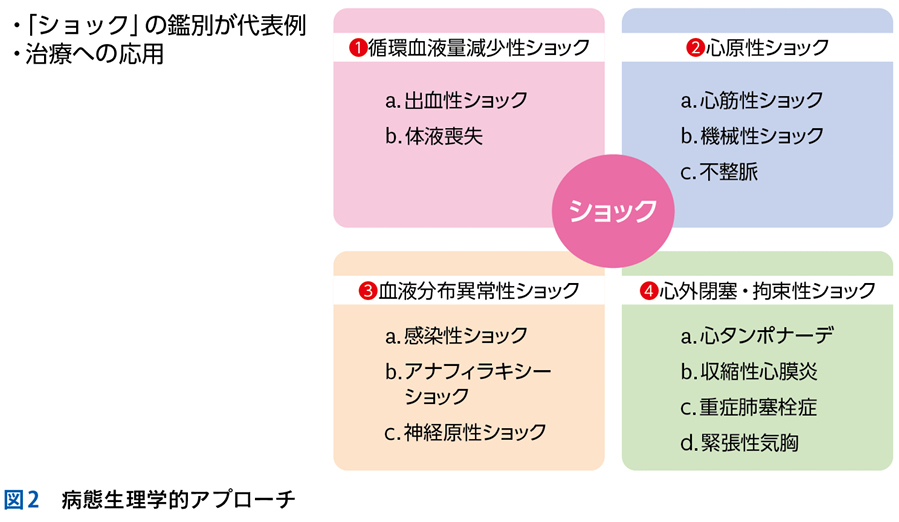

▶ 筆者の提唱する,分析的診断の「型」を図1に示した。冒頭に述べた「オリオン座を分析的に同定する手順」になぞらえ,診断推論を5つのステップにわけている。1つずつ解説しよう。